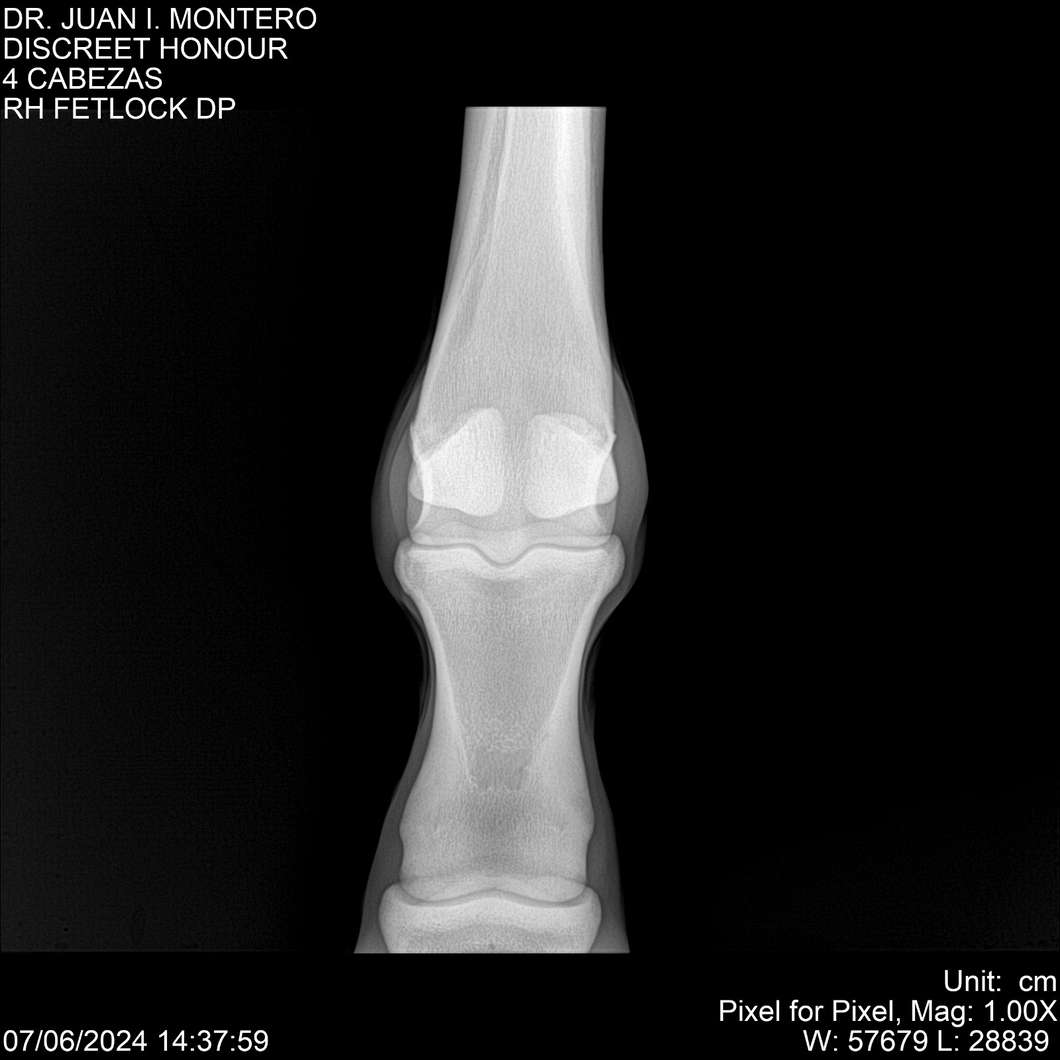

LOTE 6, DISCREET HONOUR 🔥 🔥 🔥 Lote Anterior Volver al remate Lote Siguiente Ficha Contacto Montevideo - Ficha del Lote Identificador: #281093 Categoría: Yeguarizos Montevideo - 82 Visualizaciones ClicData Contacto Empresa: Abelenda N. R., Walter Hugo Nombre*: Teléfono* : E-mail* : Mensaje Enviar Registrese gratis Este contenido Exclusivo está disponible sólo para usuarios registrados Ingresar